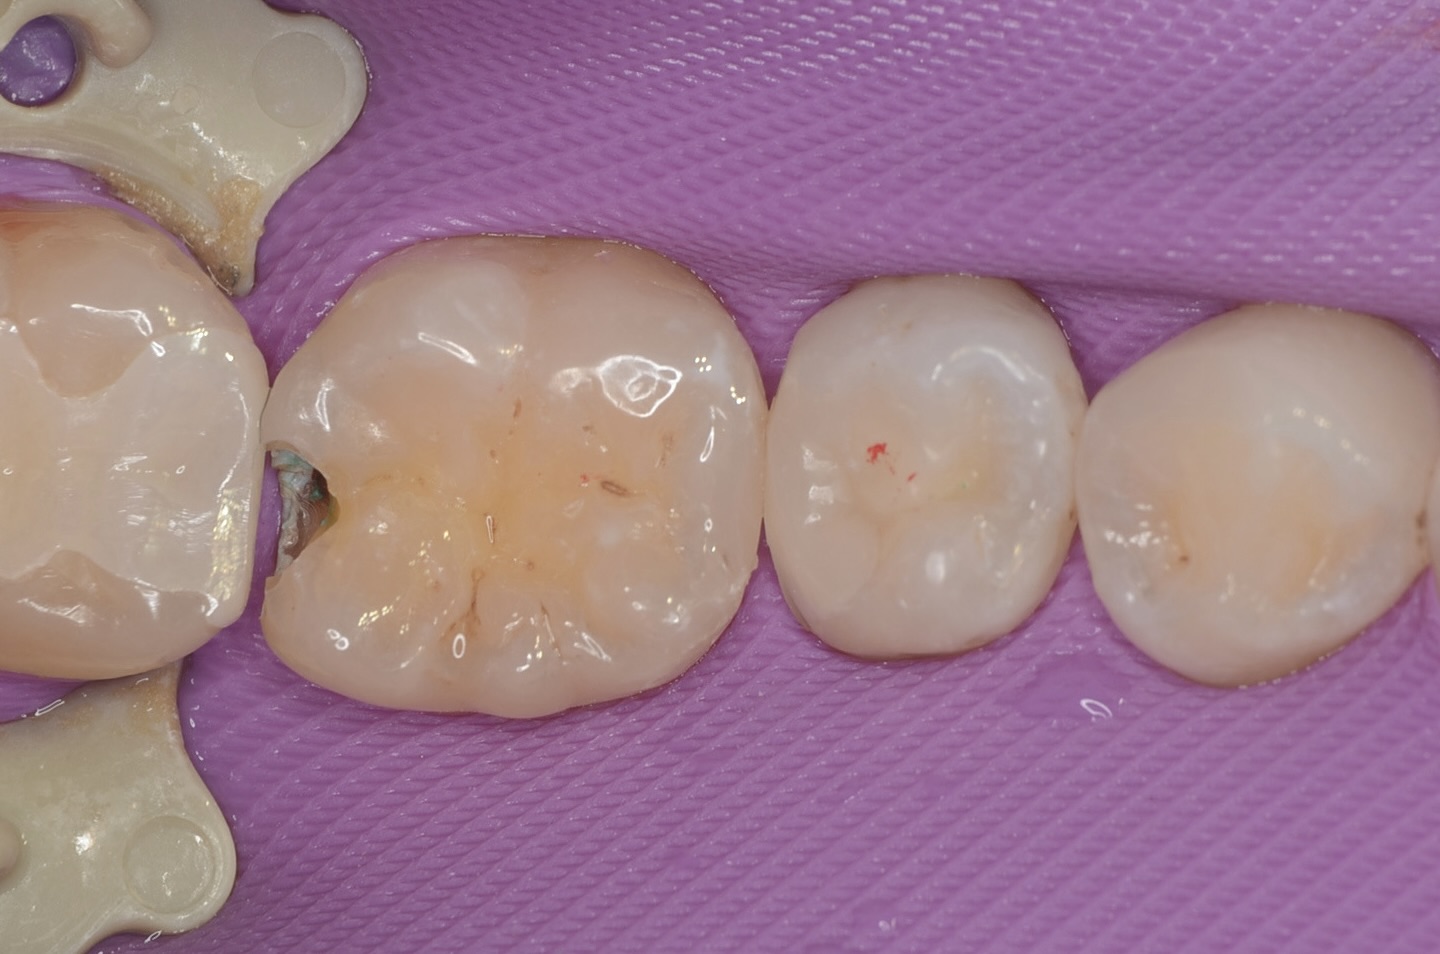

MTAセメント

数分後に自然止血しました。マイクロスコープで神経の状態を確認し保存できると判断しました。MTAセメントは硬化までに数時間かかります。 MTAセメントは弱アルカリ性で象牙祭管内の最近を殺菌します。MTAセメントを充填しました。MTAセメントは弱アルカリ性で象牙祭管内の細菌を殺菌します。また正体親和性が高くセメント質の形成を誘導します。 -

スーパーボンド

MTAセメントの効果には数時間かかるので、象牙質に強固に接着するスーパーボンドでMTAセメントを覆います。 -

マトリックス設置

透明なポリエステルテープを使い壁を作ります。 -

ダイレクトボンディング

天然歯の自然な形態を模倣してレジンを充填しました。 -